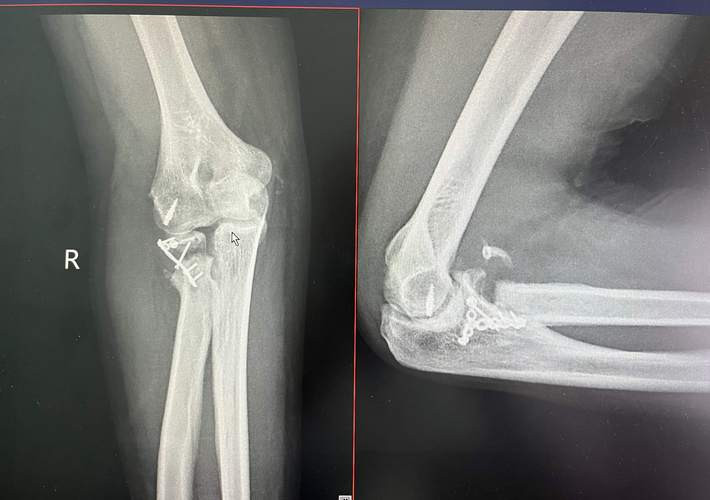

在骨折病东说念主中,60%是由骨质疏松激发的未必崩盘。像股骨颈、脊柱压缩、桡骨骨折,经常齐是“失慎”跌倒,却暴透露暗藏数年的骨骼问题。

当代医学磋商指出,当骨密度降至一定临界值,骨结构变得像蜂窝相同松散脆弱,轻轻一磕,就可能折成几片。